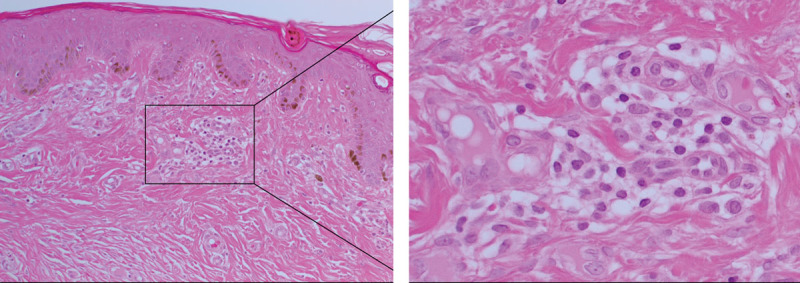

Abstract Image